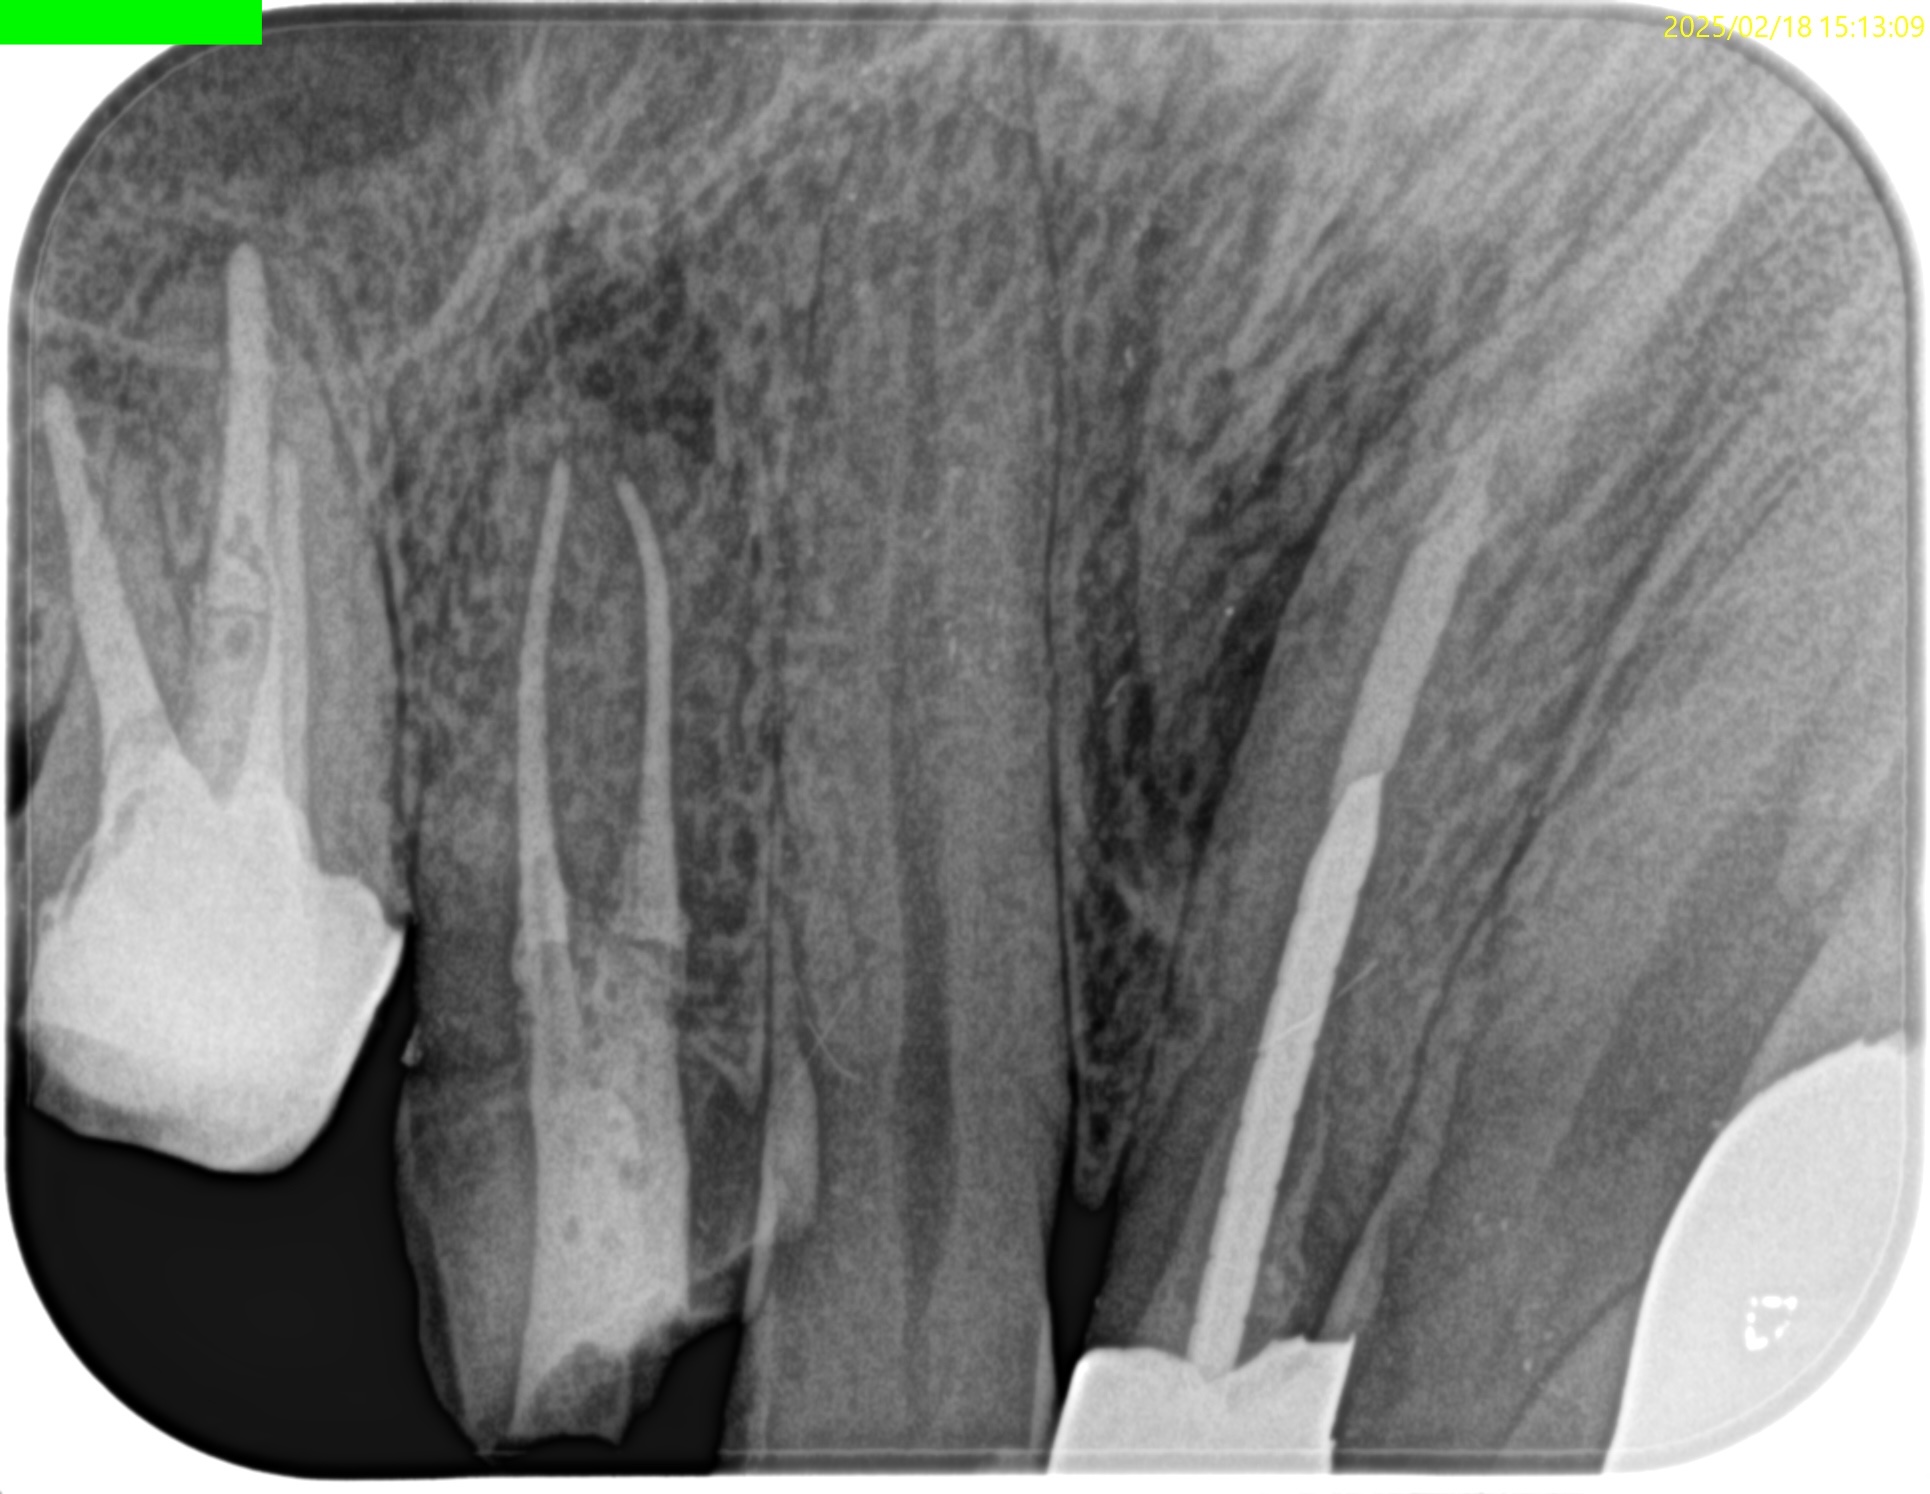

充填後、CBCTとPAを撮影した。

問題はないだろう。

#3 MB Apicoectomy 1yr recall(2026.3.19)

歯槽骨の欠損、Sinus tract, 臨床症状は消失した。

最終補綴もOKで、経過観察も終診とさせていただいた。